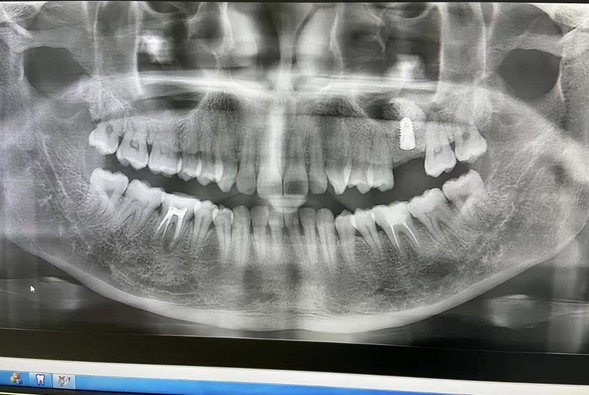

Bước đầu tiên là thăm khám tổng quát và chụp phim CT Cone Beam để đánh giá mật độ và thể tích xương hàm. Từ đó, bác sĩ lập kế hoạch cấy ghép Implant chính xác cho từng khách hàng.